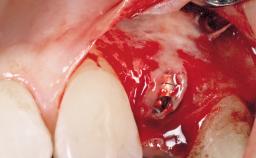

Immediate Flapless Placement of an Implant in a Maxillary Right Lateral Incisor Site

This 43-year-old male patient, a non-smoker, came to our practice because of a fracture of tooth 12 caused by a bicycle accident. Due to the combined para- and infrabony crown and root fracture, tooth extraction, and subsequent implant placement were suggested to the patient as the therapy of choice. The patient had high esthetic expectations with regard to the treatment outcome and asked for an immediate fixed provisional restoration. His individual esthetic risk profile summed up to a medium esthetic risk.

Placement Protocol Immediate implant placement

Tooth Site Maxillary incisor or canine

Socket Morphology Single-root socket

Socket Integrity Sufficient, with intact bone walls

Bone Volume Sufficient, with intact walls

Loading Protocol Immediate

Retention Screw-retained Screw-retained